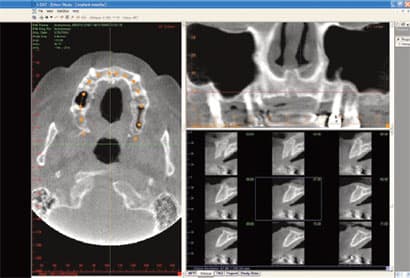

IN THE PAST, DENTAL DAYDREAMERS PONDERED THE ABILITY TO CAPTURE A 3-D IMAGE OF THE MOUTH AND TO VIEW IT FROM ALL ANGLES. The ability to rotate that 3-D mode and zoom in on details was an even greater aspiration. Then, to coordinate all of the information for integration with other applications- such as guided implant placement software-promised to add even more value to the technology. All of these benefits are not just relegated to the dental visionaries of the future. 3-D imaging is available, here and now, and is actively improving practices across all dental disciplines. IMPLANTOLOGY Jack T. Krauser, DMD: 3-D radiography has made an astonishing and

Cone Beam CT: A Breakthrough Imaging Technology for Dentistry

ABSTRACT: Accurate images of the craniofacial region are critical for the development of a diagnosis and treatment plan. The Cone Beam CT (CBCT) Scanner represents a significant advance in imaging capabilities for all disciplines of dentistry. This new-generation scanner uses computed tomography technology to provide a complete three-dimensional view of the maxilla, mandible, teeth, and supporting structures with relatively high resolution and low radiation exposure to the patient. This article discusses some of the technical aspects of CBCT and its possible dental usages. INTRODUCTION: Images of the craniofacial region comprise an important component of the dental patient record. Ideally, the imaging process begins with the development of an imaging goal. The imaging

2-D imaging (standard film and digital X-rays) has long been the standard for dental scans-despite the somewhat costly price and high radiation dosages. Now 3-D imaging technology is set to address these issues. Cone Beam technology obtains crucial information at much higher resolution using lower radiation, and is cost-effective for practitioners and patients. Indeed, such important benefits will certainly give traditional 2-D X-ray imaging a run for its money. THE INTRODUCTION OF CONE BEAM TECHNOLOGY Here's where 3-D imaging is invaluable. It lets dentists see patients' anatomies in all dimensions by creating a 360° analysis. These images give dental professionals a complete makeup of the human jaw, face, and